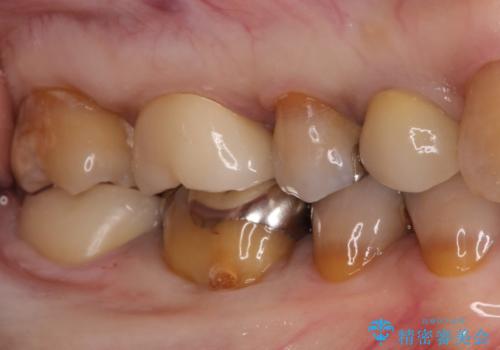

- 他院で入れたセラミックインレーがかけたことを主訴に来院されました。

他の部位にもむし歯を認めたため、優先度の高い歯から治療を行っております。

咬合力が強くかかる部分には欠けるリスクのほとんどない金属を用いることが最良ですが審美性に劣ります。

今回は白い材料での修復を希望されたため、欠けるリスクが高いセラミックインレーは避け、セラミッククラウンにて治療を行いました。